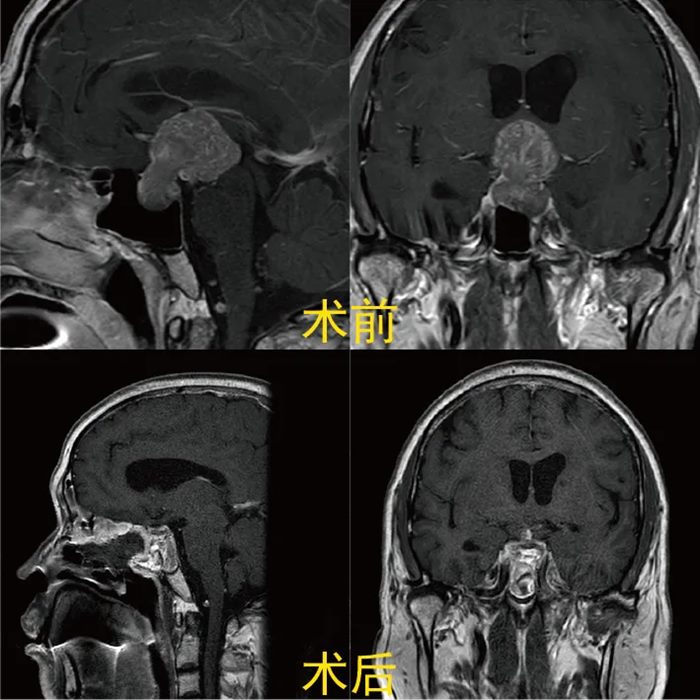

案例1:哑铃形巨瘤的"三明治修复术"

患者困境:52岁男性,肿瘤如"哑铃"卡在颅底,压迫视神经导致双眼失明,传统开颅手术风险极高。

技术突破:

内镜经鼻蝶入路:通过鼻腔这个"天然通道",将手术创伤缩小到钥匙孔大小。

三明治重建技术:人工硬脑膜(基础层)+自体阔筋膜(加固层)+带蒂鼻中隔黏膜瓣(覆盖层),构建三重防护屏障。

手术成果:

术后24小时:MRI显示肿瘤全切,无残留

视力恢复:从双目失明到重见光明

零并发症:无脑脊液漏,1周出院